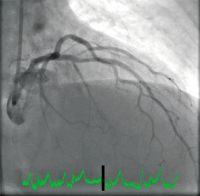

Koronarangiographie

Abbildung 1: Initiale Koronarangiographie mit Verschluss der mittleren LAD.

Keywords: KoronarangiographieLAD

LAD